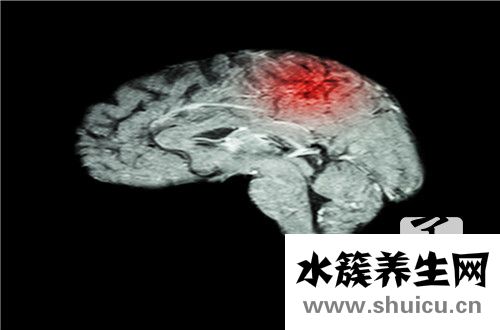

腦梗死對人體健康非常有害。在嚴重的情況下,會出現大面積腦梗塞和小腦突出。腦梗死的特點是“四高一高”,即高發病率、高致殘率、高復發率和高死亡率。雖然腦梗死的治療方法多種多樣,但半數以上的腦...